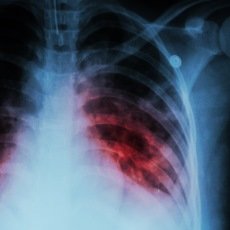

Diagnosing TB involves several methods, including skin or blood tests (IGRAs), chest X-rays, and sputum cultures.

TB chest or pulmonary tuberculosis caused by Mycobacterium tuberculosis. Primarily TB bacteria attack the lungs and then it spreads to other organs. Tuberculosis in the chest most commonly involves the lungs followed by lymph nodes, chest wall, cardiac, breast, and skeletal involvement can also occur in the thorax.

Delaying a visit to the doctor for proper tests can allow TB to spread further in the body and to others. Tests like chest X-rays, sputum analysis, and blood tests are essential for early detection.